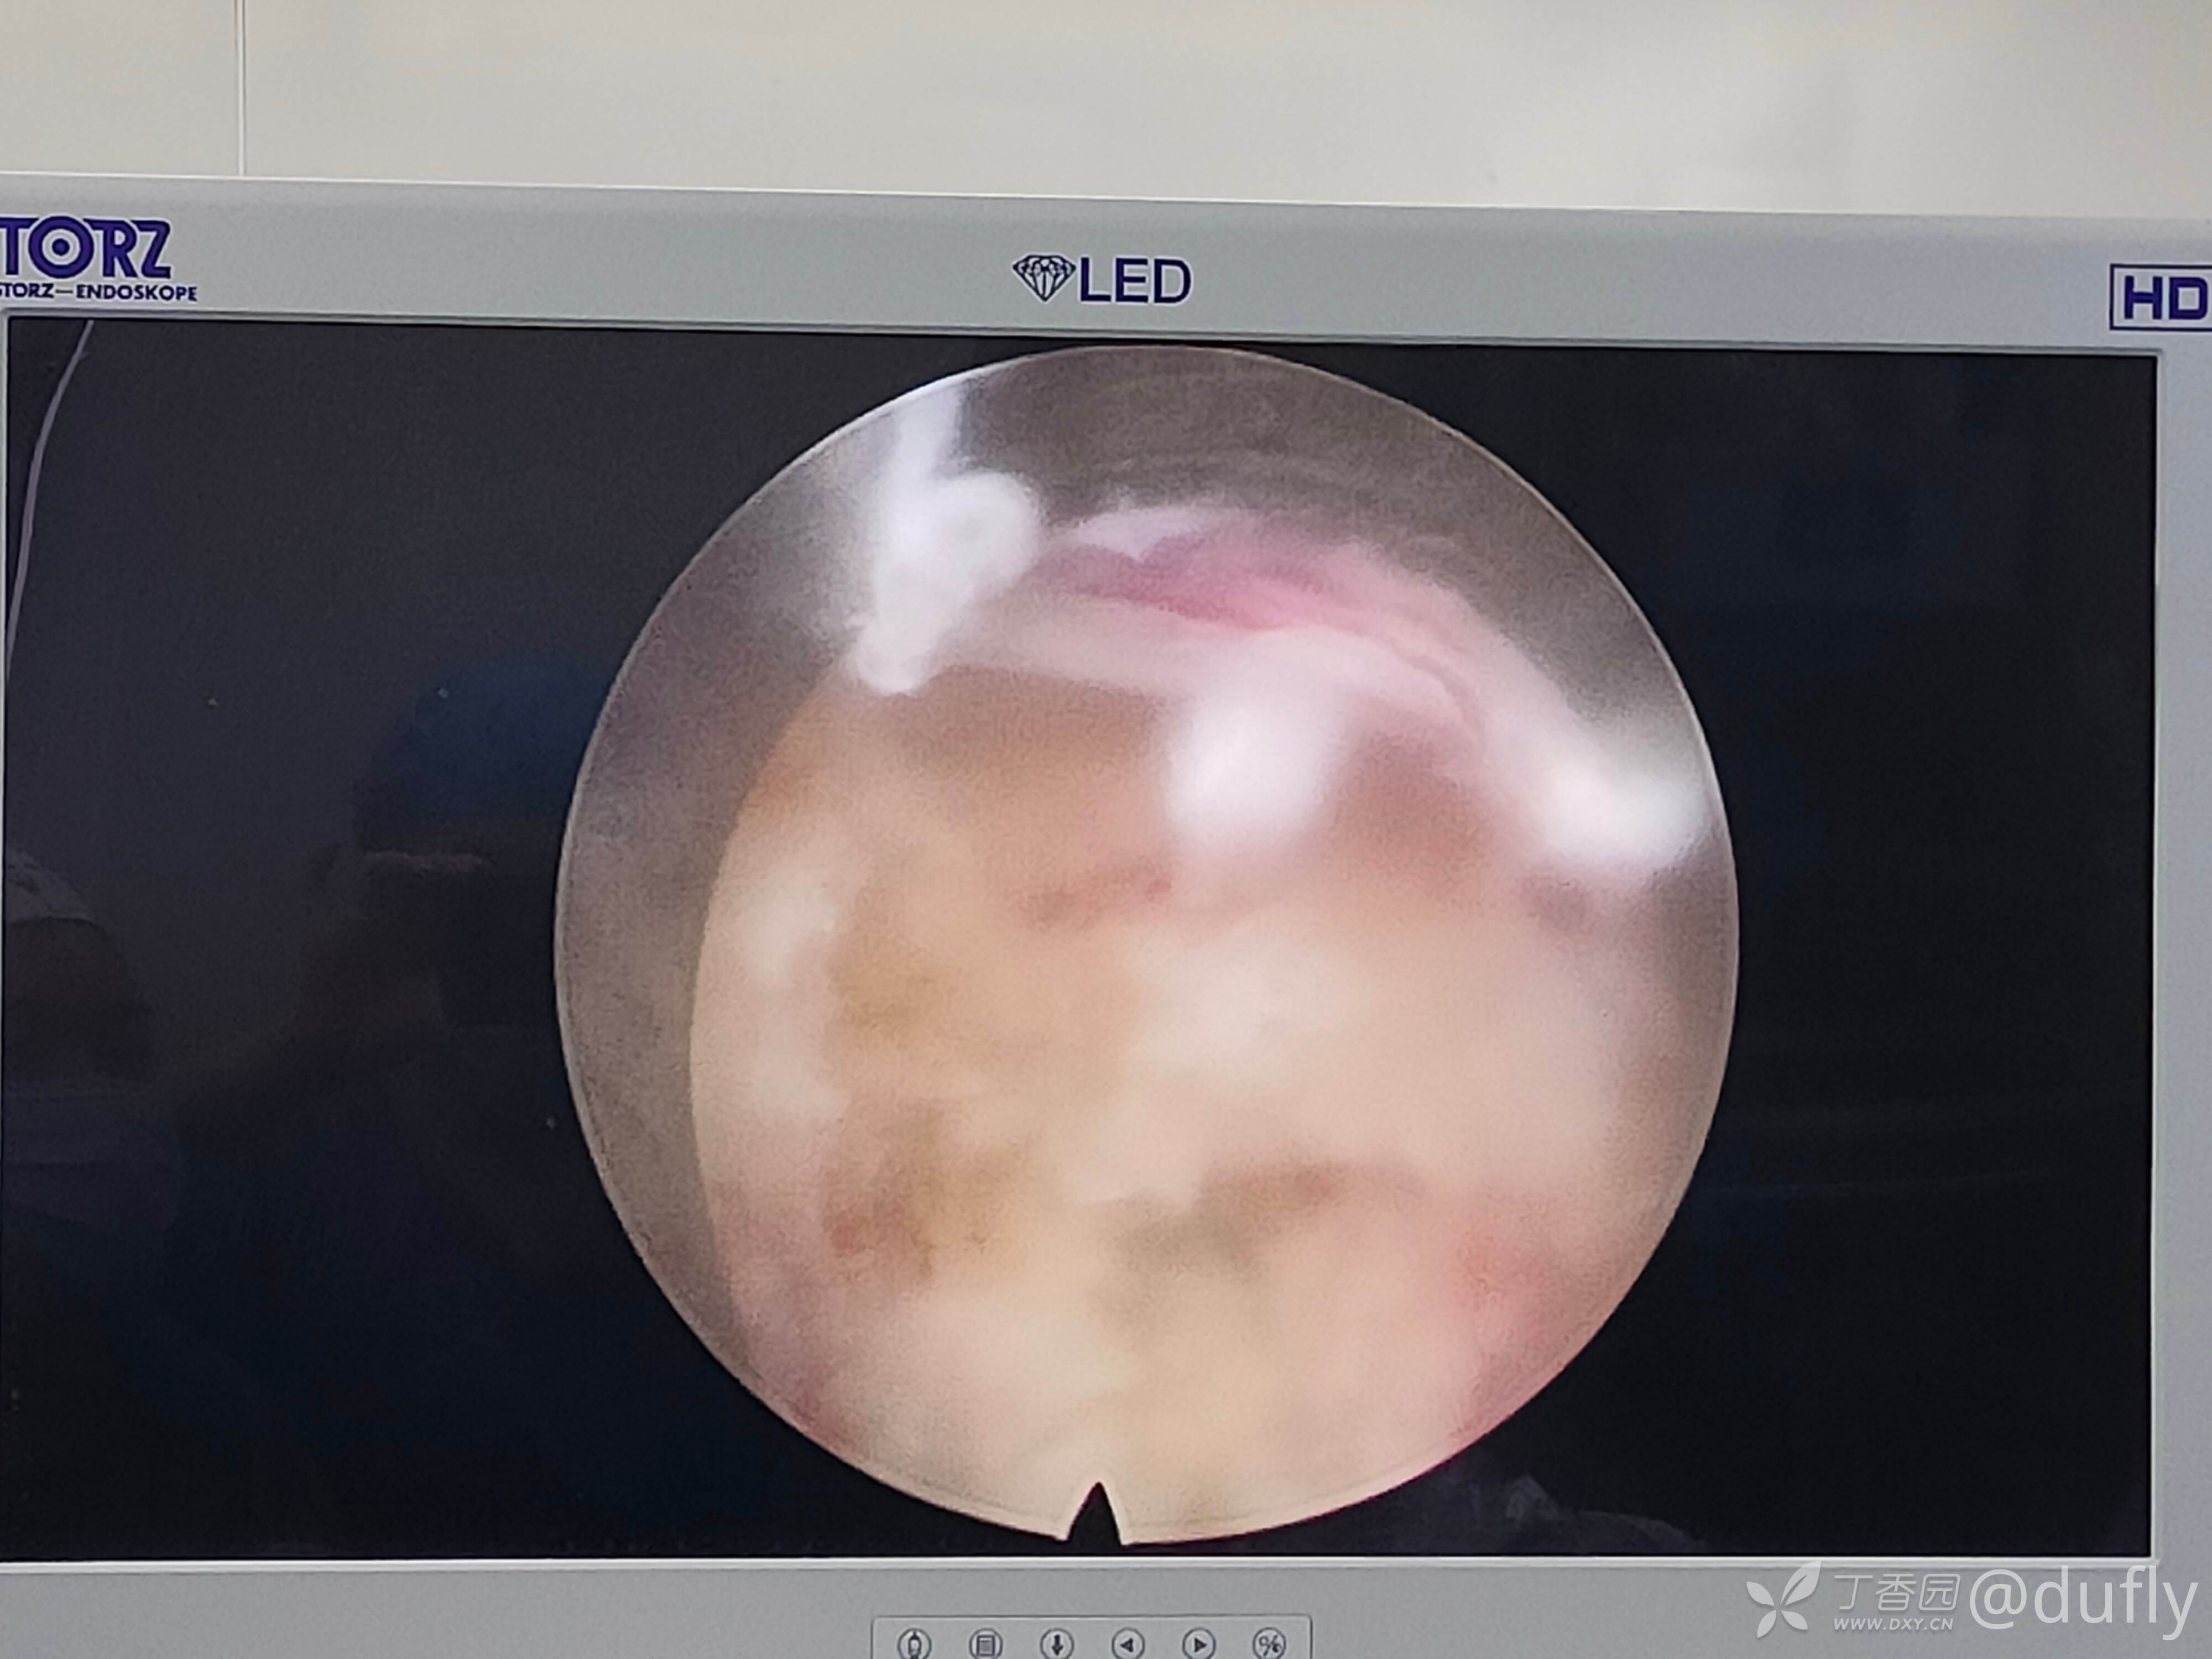

因为腰5骶1是极外侧突出,所以减压靶点是椎间孔上部,显露出口根。穿刺到骶1上关节突肩部,去除上关节突肩部和腹侧骨质,向头端分离,取出出口根下方的髓核。发现两块较大的突出髓核。

再经椎间孔入路处理腰45的腹侧压迫。椎间盘后缘突出钙化,在去除部分关节突以后,显露行走根和硬膜囊。

完成腹侧的减压。在咬除硬膜腹侧骨化的突出椎间盘的时候有很大的困难。其中发生止血困难两次。每次止血时间都超过10分钟。最后减压至1区,没有充分减压到对侧。